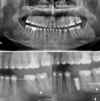

Diş Çürükleri

Diş Eksikliği

Periimplantitis

Peri-İmplant Mukozitis

Çene Kistleri

Implant tedavisi